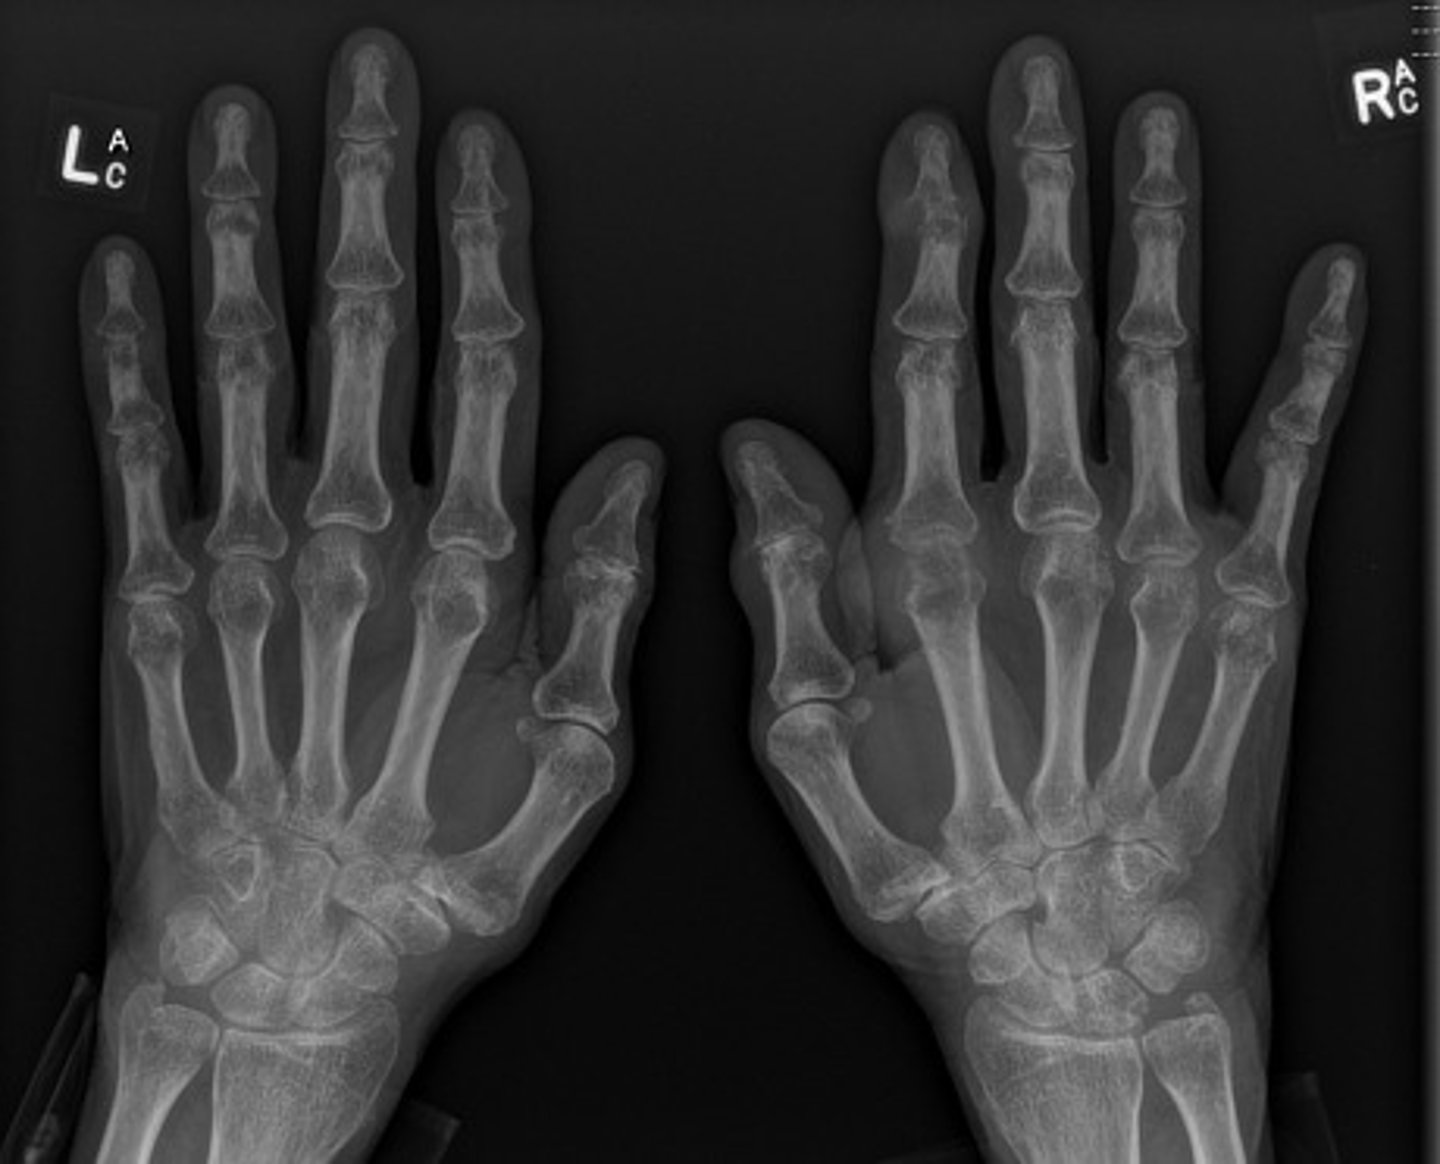

- Erosion of DIP of right digit 2 starting to wrap around

- Dense soft tissue swelling of right digit 2

- Erosion DIP of left digit 2

- Erosion of left ulnar styloid process

- Periarticular osteopenia

What are the abnormal findings on the hand films?

Gout

Diagnosis?